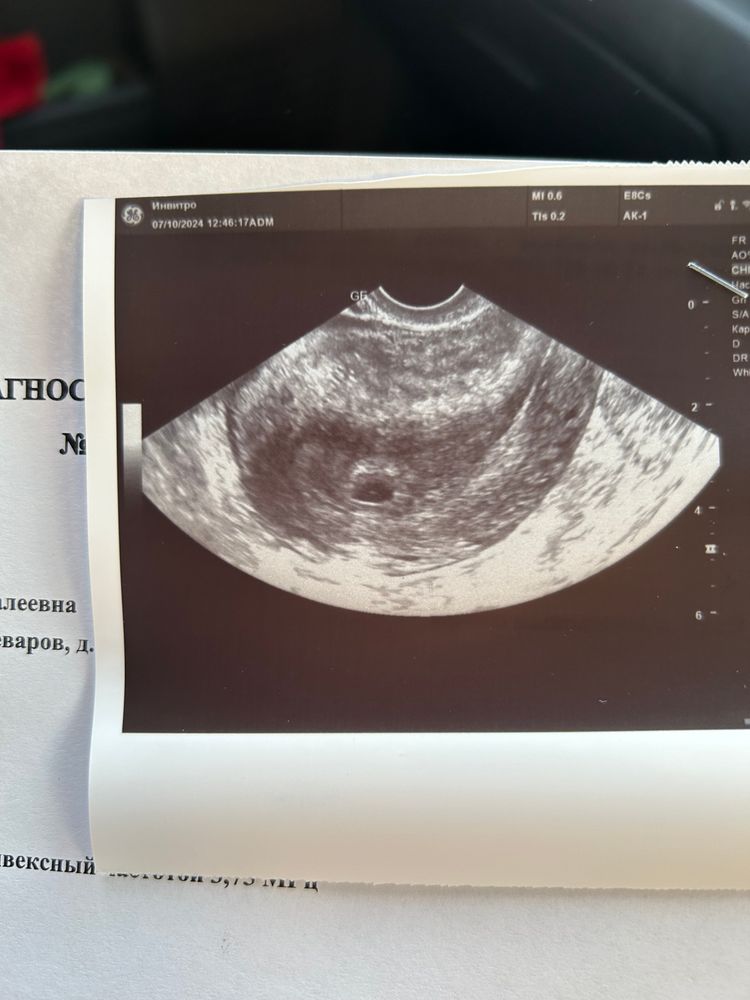

Девочки всем спасибо за советы , я сходила в клинику на узи , я счастлива , беременность маточная , эмбрион еще пока не видно но это нормально для такого срока, с учетом того что поздняя овуляция была Изображение Изображение

Очень мало описано. Нет жёлтого тела. Но большой левый яичник. Шейка 27 мм? Всегда такая? Не видели абдоминально на таком сроке. Делали вагинально всегда. Сделайте в другом месте.

Сходите в другое место и не ждите неделю, на таком сроке делают трансвагинально узи, так как абдоминально можно как раз не увидеть, зачем делали таким способом непонятно. У вас и про ЖТ ничего не написано, я бы уже переделала в другом месте